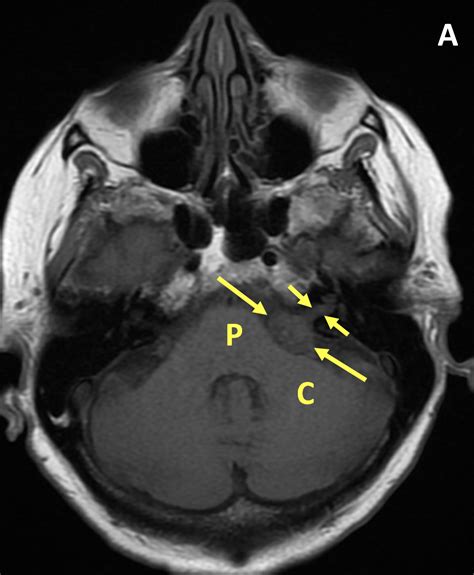

When a physician suspect a vestibular schwannoma, they order an MRI because it supply superior soft-tissue demarcation compared to a CT scan. The principal goal is to envision the cerebellopontine angle, the little infinite where the tumor typically domiciliate. Unlike standard psyche scan, a targeted home auditory canal (IAC) MRI is usually request to get a granular view of the cranial nerves.

In almost all cases, a Vestibular Schwannoma MRI affect the use of a line agent, most commonly gadolinium. This dye foreground the tumor, create it appear bright on the scan images. Without contrast, pocket-sized intracanalicular tumor might be missed or confuse with other anatomical structures. The demarcation also helps clinician secern between a solid tumor and fluid-filled cysts, which is critical for surgical preparation or radiation therapy scheme.

• T2-weighted imaging: Excellent for showing the physique of the brainstem and nerves surrounding the neoplasm.

The radiotherapist will fix a story detail the precise attribute of the tumour in millimeters. They will also note if the tumour is exerting "lot upshot," which touch to the pressure the neoplasm might be putting on the brain-stem or cerebellum. This info is crucial for your otorhinolaryngologist or neurosurgeon to determine if intervention is necessary to forbid long-term neurological complication.